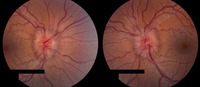

Idiopathic intracranial hypertension

Frisén stage 4

From the personal collection of Dr M. Wall; used with permission